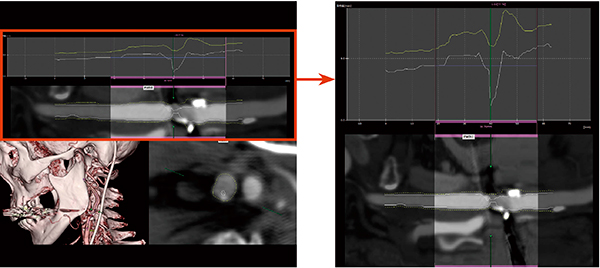

■NASCET(North American Symptomatic Carotid Endarterectomy Trial)計測

内頸動脈狭窄症は,食生活の変化などにより,わが国においても増加傾向を示している。2008年にCAS(Carotid Artery Stenting:頸動脈ステント)が認可されたことや,CT画像の画質向上などにより,血管撮影画像だけでなく,CT画像でも狭窄率の測定が積極的に行われるようになっている。VINCENTでは,血管CPR解析アプリケーションで,頸動脈狭窄症の外科的治療の指標となるNASCET計測が可能となった(図5)。内頸動脈遠位部と狭窄部を2点指定することで,値を算出することができる。また,NASCET法以外の狭窄率測定も前バージョンと同様に可能となっており,施設の運用に応じて,適宜使い分けることができるようになっている。

図5 血管CPR解析のNASCET計測画面

内頸動脈の正常径を指定し,狭窄率を算出する。